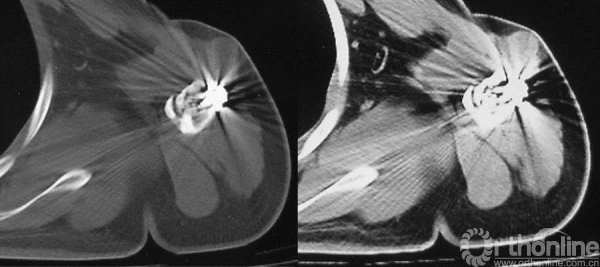

图13-9 病例一入院时CT轴位骨窗、软组织增强窗(第一次术后6个月)

明显异型性及间变的肿瘤组织,诊断考虑为骨肉瘤。

高度间变的多角形细胞间骨样组织,片状坏死,符合普通型骨肉瘤。